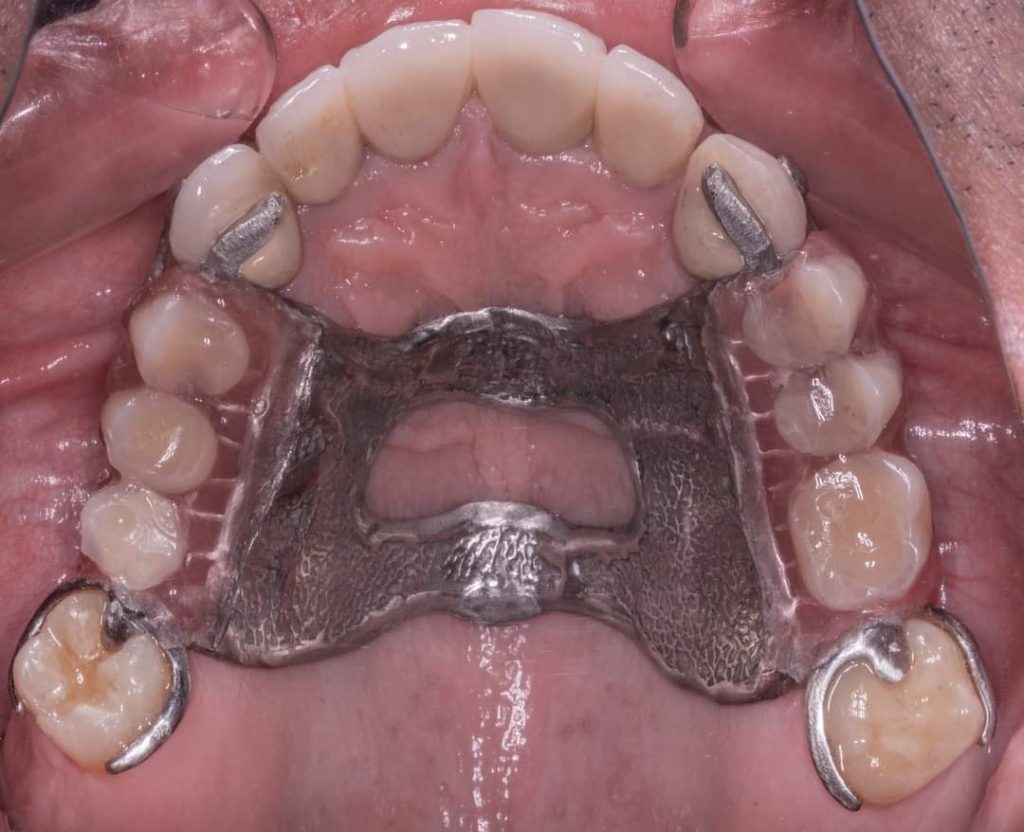

Metallic RPD done on surveyed crowns no.13,17… 23,27

Aker claps on 17,27

Cingulum rest seat and RPI clasp on surveyed crowns